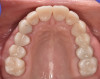

At a clinic treating patients in an underserved population, a 54-year-old female patient presented requesting extraction of all of her teeth and fabrication of dentures for her long-term restorations. The patient had a history of breast cancer, which had been treated with chemotherapy. She believed that full dentures would be an appropriate treatment option for her, owing to the poor state of her oral health and dentition and because she had limited financial resources and did not think that she could afford restoration of her teeth. The patient reported that she had experienced depression and alcohol abuse because of her cancer diagnosis, and that she had neglected her dental care during the course of her cancer treatment, resulting in generalized moderate-to-severe caries with moderate wear due to bruxism (Figure 1 through Figure 5). She also presented with significant staining of her remaining dentition due to the alcohol abuse.

Fig. 2